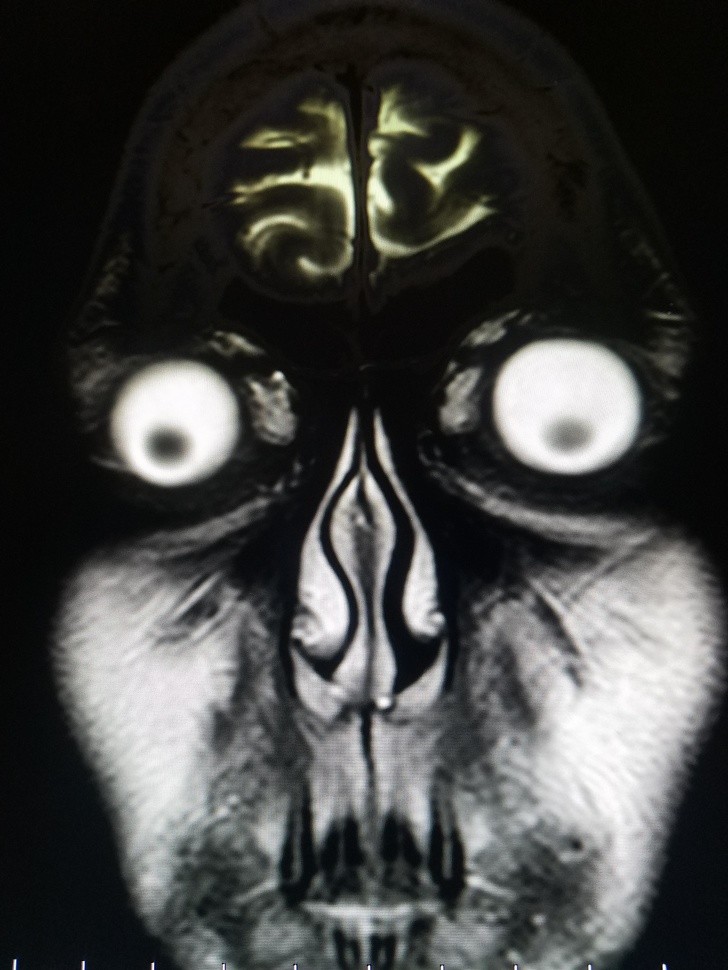

Humans are truly strange creatures and incredibly bizarre things can happen to us. These x-rays will shock even those who think they've seen it all.

Radiologists are already quite accustomed to seeing on X-rays strange things and some of these that we have collected for you in the gallery did not surprise them at all. Here is 15+ hacked and sometimes shocking x-rays.